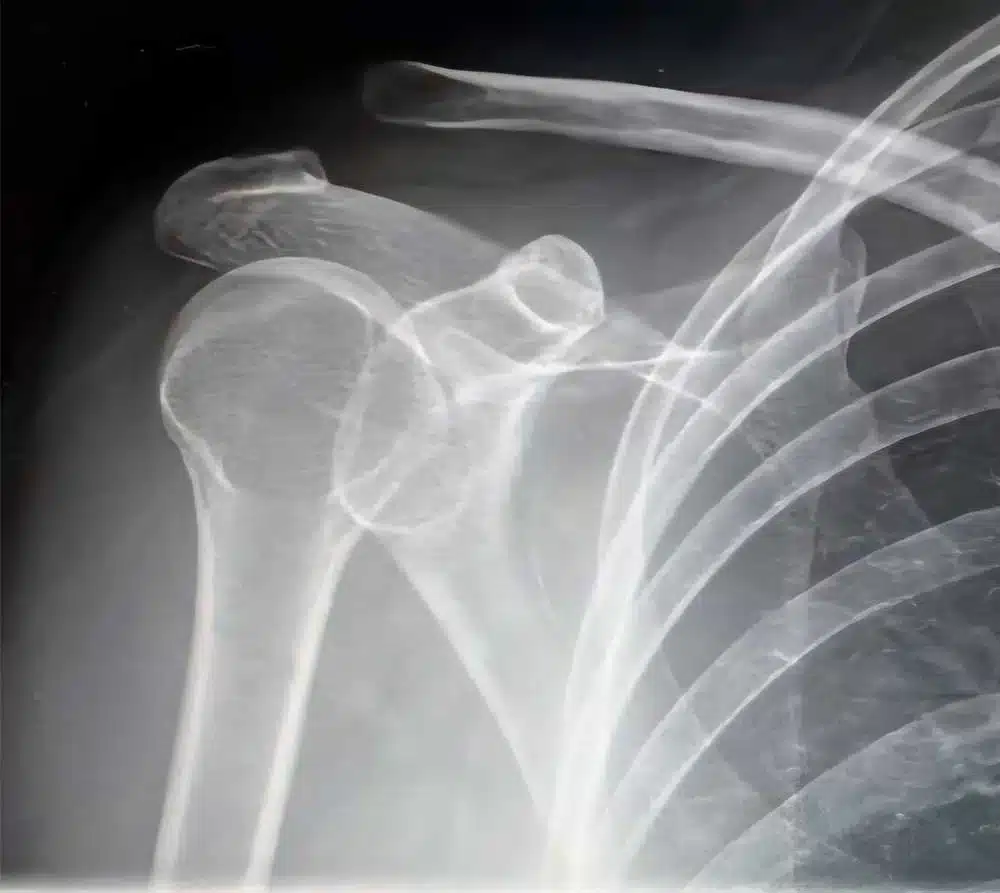

La disjonction acromio-claviculaire (ou DAC) correspond à une perte de contact anormale entre la clavicule et l’acromion, deux os situés au sommet de l’épaule.

L’articulation est stabilisée par le ligament acromio-claviculaire, les ligaments coraco-claviculaires (trapezoïde et conoïde) et les muscles environnants, notamment le deltoïde et le trapèze. Ceci permet une stabilité verticale, horizontale et rotatoire de l’épaule.